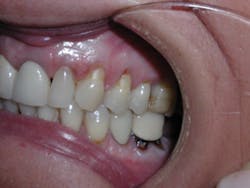

Four weeks later, Evin began his clear aligner treatment (see Figure 1). He was seen for follow-up clear aligner visits at six-week intervals until his treatment was completed. During his clear aligner treatment, Evin maintained three-month recalls with the hygienist. His home care was excellent, in part due to the benefit of aligners being removable.

Figure 1

The six-week follow-up visits with Evin were eye-opening! I had the opportunity to observe his periodontal condition improve at each interval. After 30 aligners, or 15 short months, Evin's clear aligner orthodontic treatment was completed and final photos were taken. His bite was checked to confirm we had achieved our initial goal. Evin now had the appropriate overbite, overjet, and class I occlusion with proper posterior intercuspation with no interferences.

Evin is a perfect example of this. He always had beautiful teeth. Dr. Miraglia could see that they were just in the wrong place! Insufficient space, as a result of improper arch forms is the cause of crowding, not "crooked" teeth (see Figure 1).